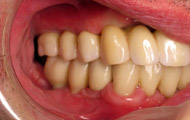

Situation clinique initiale